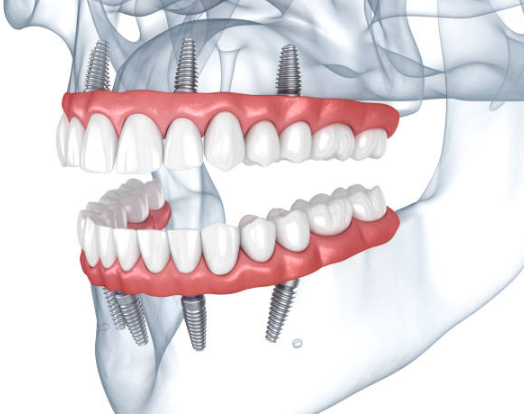

임플란트는 상실된 치아를 인공치아의 식립을 통해 다시 건강하게 사용할 수 있게 만드는 것을 뜻합니다.

임플란트는 크게 세 부분으로 나뉘며, 치아 뿌리를 대신하는 구조물인 임플란트 (인공치근), 그 위에 체결을 하는 보철기둥 (지대주), 마지막으로 그 위에 씌우는 보철물 (크라운)이 있습니다.